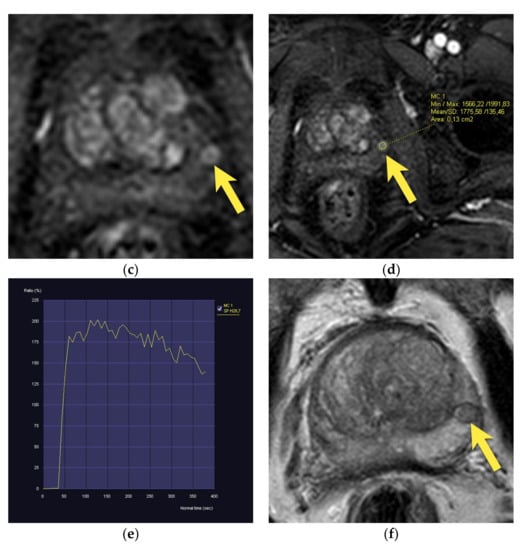

| Type | Location | |

|---|---|---|

| Anatomic structures | Anterior fibromuscular stroma | Anterior prostate |

| Central zone | Base of the prostate and posterior middle peripheral zone | |

| Periprostatic venous plexus | Peripheral zone | |

| Benign pathology | Stromal BPH nodule | Transition zone and occasionally the peripheral zone (as ectopic BPH nodule) |

| Ectopic BPH nodule | Peripheral zone | |

| Diffuse and focal prostatitis | Peripheral zone is more often involved, adjacent transition zone may also be affected | |

| Abscess | Peripheral or transition zone | |

| Hemorrhage | Peripheral or transition zone |